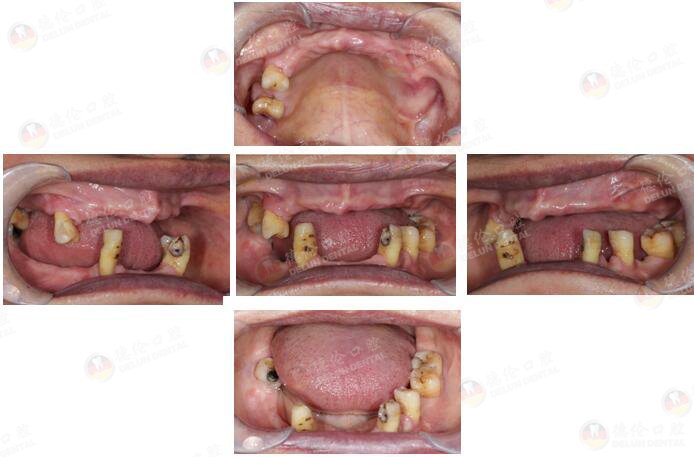

全口无牙颌种植

患者情况

许女士 65岁

牙齿症状:全口多牙缺失十余年。

10余年前因牙周炎致全口多牙拔除,之后利用活动假牙修复,现在出现活动假牙固位差、牙龈游走性压痛等情况,希望做种植牙修复。

治疗方式:倾斜植体避开左侧上颌窦、整体支架修复、数字化3D导板种植